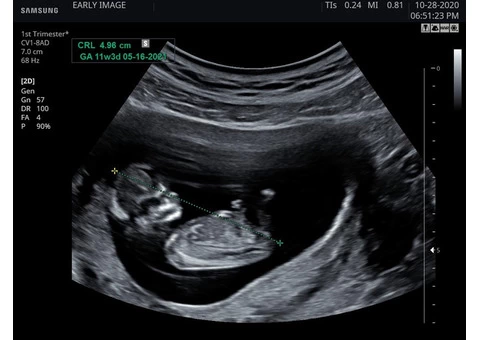

If you're experiencing anxiety or worries about your pregnancy, our reassurance scan can help provide you with the peace of mind you need. At Early Image, our experienced ultrasound specialists use advanced technology to examine your baby and ensure they are developing healthily.

Our reassurance scan is recommended for women who are at least six weeks pregnant and are experiencing any concerns, such as bleeding or cramping. It can also be an opportunity for parents who have experienced previous miscarriages or stillbirths to alleviate their anxiety.